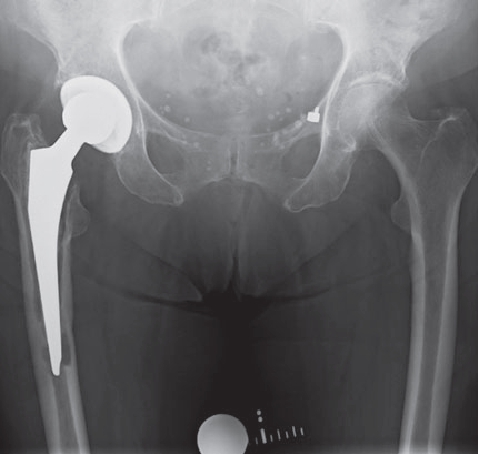

However, infections often go unnoticed for many weeks, so that removal of the prosthesis is unavoidable. Depending on the pathogen and its sensitivity, a placeholder containing antibiotics is then implanted, which remains in place for 6 weeks. Antibiotics in tablet form must then also be taken for this period. However, it is not necessary for a patient to remain in the hospital during this entire period. If home care is not possible, for example, it is also possible to organize this in close cooperation with our social services. After 6 weeks it is generally possible to reimplant a prosthesis, provided that the blood values show that the infection is under control. Antibiotics must then be taken again for 6 weeks after surgery. Which antibiotics are taken is determined in close cooperation with colleagues in microbiology and clinical pharmacology, with whom regular rounds and therapy checks are carried out. These therapeutic measures are carried out in a special area of the clinic using the most modern methods.